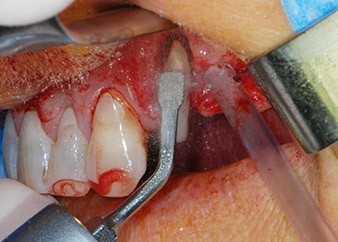

След един месец, в деня на операцията, болката и възпалението в зъб 24 е минимално, но подвижността в Miller class 2 е на лице. След отваряне на ламбата и почистването на периапикалната и перирадикуларната тъкани, обхватът на костния дефект стана очевиден (Фиг. 2 и 3).

тотална загуба на кост и захват

Фиг. 2 и 3: След повдигане на ламбото, един месец след ендодонтския преглед и прилагане на цялостна периодонтална терапия в цялата уста, букалният корен на зъб 24 разкри тотална загуба на кост и захват.

Въпреки това, ние се придържахме към първоначалния си план да запазим и двата зъба като абатмънти за временен мост по време на 6-месечната остеоинтеграция на имплантите. При повторна интервенция, ситуацията трябва да се преразгледа. Първо, в опит да се овладее ендо-перио проблема, останалата повърхност на зъба е внимателно обработена с пиезохирургично оборудване (Piezomed, W&H, използван с накрайник S1 под формата на шпатула, първоначално проектиран за ерозия на латералната синусна стена) (Фиг. 4).